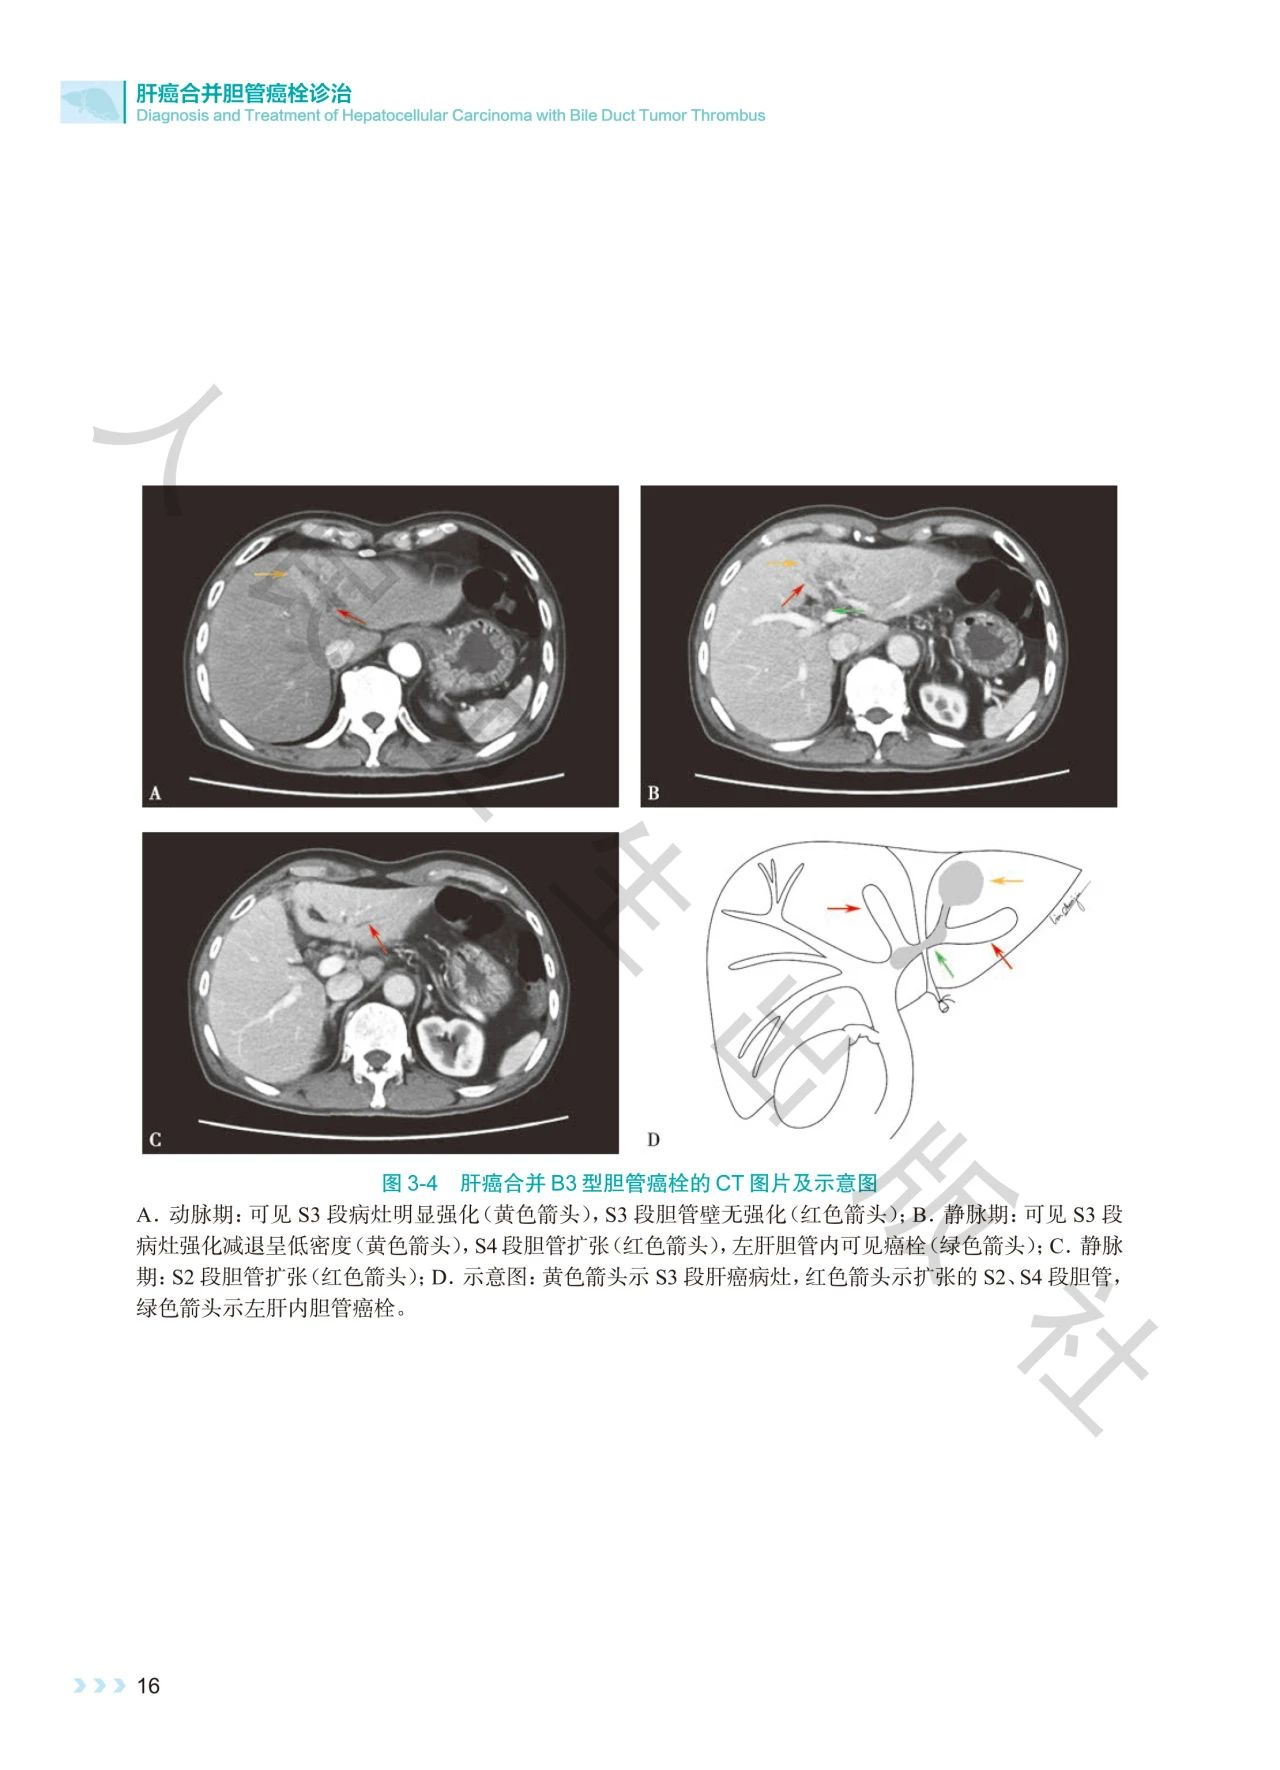

《肝癌合并胆管癌栓诊治》深入探讨了肝癌合并胆管

癌栓诊治领域的焦点问题。书中通过影像图、示意图

、手术图,详细阐述了不同分型胆管癌栓的影像学特

点及手术方式,提出q形胆总管切开取栓方法,强调解

本书通过丰富的示意图、影像图和手术图,对肝癌合

并胆管癌栓的分型、诊断策略、治疗方法等进行了深

入剖析,全面系统地总结了肝癌合并胆管癌栓领域的